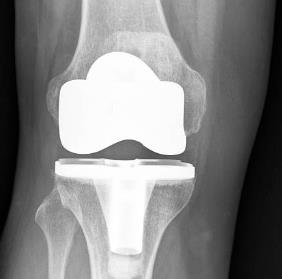

報告目錄 全球及中國人工膝關(guān)節(jié)部件細分市場深度研究報告 2022 1 人工膝關(guān)節(jié)部件行業(yè)現(xiàn)狀、背景 1.1 人工膝關(guān)節(jié)部件行業(yè)定義與特性 1.2 人工膝關(guān)節(jié)部件行業(yè)技術(shù)壁壘 1.3 人工膝關(guān)節(jié)部件產(chǎn)業(yè)鏈全景 1.3.1 全球人工膝關(guān)節(jié)部件上游企業(yè)及上游產(chǎn)品技術(shù)特點 1.3.2 全球人工膝關(guān)節(jié)部件下游企業(yè)及行業(yè)分布 1.4 人工膝關(guān)節(jié)部件產(chǎn)品細分及各細分產(chǎn)品的頭部企業(yè) 2 人工膝關(guān)節(jié)部件行業(yè)頭部企業(yè)分析 2.1 全球人工膝關(guān)節(jié)部件主要生產(chǎn)商生產(chǎn)基地分布 2.2 DePuyInternationalltd 2.2.1 DePuyInternationalltd 企業(yè)概況 2.2.2 DePuyInternationalltd 產(chǎn)品規(guī)格及特點 2.2.3 DePuyInternationalltd 銷量、銷售額及價格(2017-2021) 2.2.4 DePuyInternationalltd 市場動態(tài) 2.3 Chi-YiInvestmentCo.Ltd. 2.3.1 Chi-YiInvestmentCo.Ltd. 企業(yè)概況 2.3.2 Chi-YiInvestmentCo.Ltd. 產(chǎn)品規(guī)格及特點 2.3.3 Chi-YiInvestmentCo.Ltd. 銷量、銷售額及價格(2017-2021) 2.3.4 Chi-YiInvestmentCo.Ltd. 市場動態(tài) 2.4 MicroPortScientificCorporation 2.4.1 MicroPortScientificCorporation 企業(yè)概況 2.4.2 MicroPortScientificCorporation 產(chǎn)品規(guī)格及特點 2.4.3 MicroPortScientificCorporation 銷量、銷售額及價格(2017-2021) 2.4.4 MicroPortScientificCorporation 市場動態(tài) 2.5 SAMOS.p.A 2.5.1 SAMOS.p.A 企業(yè)概況 2.5.2 SAMOS.p.A 產(chǎn)品規(guī)格及特點 2.5.3 SAMOS.p.A 銷量、銷售額及價格(2017-2021) 2.5.4 SAMOS.p.A 市場動態(tài) 2.6 MedactaGroup 2.6.1 MedactaGroup 企業(yè)概況 2.6.2 MedactaGroup 產(chǎn)品規(guī)格及特點 2.6.3 MedactaGroup 銷量、銷售額及價格(2017-2021) 2.6.4 MedactaGroup 市場動態(tài) 2.7 Smith&NephewOrthopaedicsAG 2.7.1 Smith&NephewOrthopaedicsAG 企業(yè)概況 2.7.2 Smith&NephewOrthopaedicsAG 產(chǎn)品規(guī)格及特點 2.7.3 Smith&NephewOrthopaedicsAG 銷量、銷售額及價格(2017-2021) 2.7.4 Smith&NephewOrthopaedicsAG 市場動態(tài) 2.8 Biomet,Inc 2.8.1 Biomet,Inc 企業(yè)概況 2.8.2 Biomet,Inc 產(chǎn)品規(guī)格及特點 2.8.3 Biomet,Inc 銷量、銷售額及價格(2017-2021) 2.8.4 Biomet,Inc 市場動態(tài) 2.9 WrightWrightMedicalGroupNV 2.9.1 WrightWrightMedicalGroupNV 企業(yè)概況 2.9.2 WrightWrightMedicalGroupNV 產(chǎn)品規(guī)格及特點 2.9.3 WrightWrightMedicalGroupNV 銷量、銷售額及價格(2017-2021) 2.9.4 WrightWrightMedicalGroupNV 市場動態(tài) 2.10 LimaCorporate 2.10.1 LimaCorporate 企業(yè)概況 2.10.2 LimaCorporate 產(chǎn)品規(guī)格及特點 2.10.3 LimaCorporate 銷量、銷售額及價格(2017-2021) 2.10.4 LimaCorporate 市場動態(tài) 2.11 CorinGroup 2.11.1 CorinGroup 企業(yè)概況 2.11.2 CorinGroup 產(chǎn)品規(guī)格及特點 2.11.3 CorinGroup 銷量、銷售額及價格(2017-2021) 2.11.4 CorinGroup 市場動態(tài) 2.12 StrykerCorporation 3 全球人工膝關(guān)節(jié)部件細分應用領(lǐng)域 3.1 全球人工膝關(guān)節(jié)部件細分應用領(lǐng)域銷售現(xiàn)狀及預測(2017-2027年) 3.1.1 全球人工膝關(guān)節(jié)部件細分應用領(lǐng)域銷量及占比(2020-2021年) 3.1.2 醫(yī)院 3.1.3 診所 3.1.4 …... 3.2 中國人工膝關(guān)節(jié)部件細分應用領(lǐng)域銷售現(xiàn)狀及預測(2017-2027年) 3.2.1 中國人工膝關(guān)節(jié)部件細分應用領(lǐng)域銷量及占比(2020-2021年) 3.2.2 醫(yī)院 3.2.3 診所 3.2.4 …... 3.3 全球人工膝關(guān)節(jié)部件行業(yè)驅(qū)動因素分析 3.3.1 人工膝關(guān)節(jié)部件行業(yè)下游細分賽道需求拉動作用分析 3.3.2 技術(shù)進步對人工膝關(guān)節(jié)部件行業(yè)的帶動作用分析 3.3.3 全球及中國人工膝關(guān)節(jié)部件行業(yè)利好政策分析 4 全球人工膝關(guān)節(jié)部件市場規(guī)模分析 4.1 全球人工膝關(guān)節(jié)部件銷售現(xiàn)狀及預測 4.1.1 全球人工膝關(guān)節(jié)部件銷量及增長率(2017-2027年) 4.1.2 全球各類型人工膝關(guān)節(jié)部件銷量及市場占比(2017-2027年) 股骨端植入物 脛骨關(guān)節(jié)面襯墊 脛骨基座 髕骨植入物 其他 4.1.3 全球各類型人工膝關(guān)節(jié)部件銷售額及市場占比(2017-2027年) 股骨端植入物 脛骨關(guān)節(jié)面襯墊 脛骨基座 髕骨植入物 其他 4.1.4 全球各類型人工膝關(guān)節(jié)部件價格變化趨勢(2017-2027年) 股骨端植入物 脛骨關(guān)節(jié)面襯墊 … ... 4.2 全球人工膝關(guān)節(jié)部件行業(yè)集中率分析 4.2.1 全球人工膝關(guān)節(jié)部件行業(yè)集中度指數(shù)(CR5、銷量)(2017-2021) 4.2.2 全球人工膝關(guān)節(jié)部件行業(yè)集中度指數(shù)(CR5、銷售額)(2017-2021) 4.3 中國人工膝關(guān)節(jié)部件行業(yè)集中率分析 4.3.1 中國人工膝關(guān)節(jié)部件行業(yè)集中度指數(shù)(CR5、銷量)(2017-2021) 4.3.2 中國人工膝關(guān)節(jié)部件行業(yè)集中度指數(shù)(CR5、銷售額)(2017-2021) 4.3.3 中國人工膝關(guān)節(jié)部件市場國外品牌占比(2017-2021) 4.3.4 中國人工膝關(guān)節(jié)部件國產(chǎn)化率(2017-2021) 5 全球主要地區(qū)人工膝關(guān)節(jié)部件市場發(fā)展現(xiàn)狀及前景分析 5.1 全球主要地區(qū)人工膝關(guān)節(jié)部件產(chǎn)量 5.1.1 全球主要地區(qū)人工膝關(guān)節(jié)部件產(chǎn)量(2017-2027年) 5.1.2 2021年全球人工膝關(guān)節(jié)部件產(chǎn)量及銷量最大的地區(qū) 5.2 全球主要地區(qū)人工膝關(guān)節(jié)部件銷量市場占比 5.2.1 全球主要地區(qū)人工膝關(guān)節(jié)部件銷量占比(2017-2027年) 5.2.2 全球主要地區(qū)人工膝關(guān)節(jié)部件銷售額占比(2017-2027年) 5.3 中國市場人工膝關(guān)節(jié)部件銷量、銷售額及增長率 5.3.1 中國市場人工膝關(guān)節(jié)部件銷量及增長率(2017-2027年) 5.3.2 中國市場人工膝關(guān)節(jié)部件銷售額及增長率(2017-2027年) 5.4 日本市場人工膝關(guān)節(jié)部件銷量、銷售額及增長率 5.4.1 日本市場人工膝關(guān)節(jié)部件銷量及增長率(2017-2027年) 5.4.2 日本市場人工膝關(guān)節(jié)部件銷售額及增長率(2017-2027年) 5.5 韓國市場人工膝關(guān)節(jié)部件銷量、銷售額及增長率 5.5.1 韓國市場人工膝關(guān)節(jié)部件銷量及增長率(2017-2027年) 5.5.2 韓國市場人工膝關(guān)節(jié)部件銷售額及增長率(2017-2027年) 5.6 東南亞市場人工膝關(guān)節(jié)部件銷量、銷售額及增長率 5.6.1 東南亞市場人工膝關(guān)節(jié)部件銷量及增長率(2017-2027年) 5.6.2 東南亞市場人工膝關(guān)節(jié)部件銷售額及增長率(2017-2027年) 5.7 印度市場人工膝關(guān)節(jié)部件銷量、銷售額及增長率 5.7.1 印度市場人工膝關(guān)節(jié)部件銷量及增長率(2017-2027年) 5.7.2 印度市場人工膝關(guān)節(jié)部件銷售額及增長率(2017-2027年) 5.8 美國市場人工膝關(guān)節(jié)部件銷量、銷售額及增長率 5.8.1 美國市場人工膝關(guān)節(jié)部件銷量及增長率(2017-2027年) 5.8.2 美國市場人工膝關(guān)節(jié)部件銷售額及增長率(2017-2027年) 5.9 歐洲市場人工膝關(guān)節(jié)部件銷量、銷售額及增長率 5.9.1 歐洲市場人工膝關(guān)節(jié)部件銷量及增長率(2017-2027年) 5.9.2 歐洲市場人工膝關(guān)節(jié)部件銷售額及增長率(2017-2027年) 6 中國人工膝關(guān)節(jié)部件細分市場及前景分析 6.1 中國各類型人工膝關(guān)節(jié)部件銷量及市場占比(2017-2027年) 6.1.1 股骨端植入物 6.1.2 脛骨關(guān)節(jié)面襯墊 6.1.3 脛骨基座 6.1.4 髕骨植入物 6.1.5 其他 6.2 中國各類型人工膝關(guān)節(jié)部件銷售額及市場占比(2017-2027年) 6.2.1 股骨端植入物 6.2.2 脛骨關(guān)節(jié)面襯墊 6.2.3 脛骨基座 6.2.4 髕骨植入物 6.2.5 其他 6.3 中國各類型人工膝關(guān)節(jié)部件價格變化趨勢(2017-2027年) 6.3.1 股骨端植入物 6.3.2 脛骨關(guān)節(jié)面襯墊 6.3.2 … ... 7 中國人工膝關(guān)節(jié)部件銷量分布狀況 7.1 中國六大地區(qū)人工膝關(guān)節(jié)部件銷量及市場占比 7.2 中國六大地區(qū)人工膝關(guān)節(jié)部件銷售額及市場占比 8 中國人工膝關(guān)節(jié)部件進出口發(fā)展趨勢 8.1 中國人工膝關(guān)節(jié)部件進口市場規(guī)模(2017-2027年) 8.2 中國人工膝關(guān)節(jié)部件出口市場規(guī)模(2017-2027年) 8.3 中國人工膝關(guān)節(jié)部件主要進口國家及進口依賴性分析 9 人工膝關(guān)節(jié)部件行業(yè)發(fā)展PESTEL分析 9.1 政治因素 9.2 經(jīng)濟因素 9.3 社會文化因素 9.4 科技因素 9.5 環(huán)保因素 9.6 法律因素 10 研究結(jié)論圖表目錄 圖:人工膝關(guān)節(jié)部件產(chǎn)品圖片 表:人工膝關(guān)節(jié)部件產(chǎn)業(yè)鏈 表:產(chǎn)品分類及頭部企業(yè) 表:DePuyInternationalltd 人工膝關(guān)節(jié)部件基本信息介紹、銷售區(qū)域、競爭對手等 表:DePuyInternationalltd 人工膝關(guān)節(jié)部件產(chǎn)品介紹 表:DePuyInternationalltd 人工膝關(guān)節(jié)部件銷量、銷售額及價格(2017-2021年) 表:Chi-YiInvestmentCo.Ltd. 人工膝關(guān)節(jié)部件基本信息介紹、銷售區(qū)域、競爭對手等 表:Chi-YiInvestmentCo.Ltd. 人工膝關(guān)節(jié)部件產(chǎn)品介紹 表:Chi-YiInvestmentCo.Ltd. 人工膝關(guān)節(jié)部件銷量、銷售額及價格(2017-2021年) 表:MicroPortScientificCorporation 人工膝關(guān)節(jié)部件基本信息介紹、銷售區(qū)域、競爭對手等 表:MicroPortScientificCorporation 人工膝關(guān)節(jié)部件產(chǎn)品介紹 表:MicroPortScientificCorporation 人工膝關(guān)節(jié)部件銷量、銷售額及價格(2017-2021年) 表:SAMOS.p.A 人工膝關(guān)節(jié)部件基本信息介紹、銷售區(qū)域、競爭對手等 表:SAMOS.p.A 人工膝關(guān)節(jié)部件產(chǎn)品介紹 表:SAMOS.p.A 人工膝關(guān)節(jié)部件銷量、銷售額及價格(2017-2021年) 表:MedactaGroup 人工膝關(guān)節(jié)部件基本信息介紹、銷售區(qū)域、競爭對手等 表:MedactaGroup 人工膝關(guān)節(jié)部件產(chǎn)品介紹 表:MedactaGroup 人工膝關(guān)節(jié)部件銷量、銷售額及價格(2017-2021年) 表:Smith&NephewOrthopaedicsAG 人工膝關(guān)節(jié)部件基本信息介紹、銷售區(qū)域、競爭對手等 表:Smith&NephewOrthopaedicsAG 人工膝關(guān)節(jié)部件產(chǎn)品介紹 表:Smith&NephewOrthopaedicsAG 人工膝關(guān)節(jié)部件銷量、銷售額及價格(2017-2021年) 表:Biomet,Inc 人工膝關(guān)節(jié)部件基本信息介紹、銷售區(qū)域、競爭對手等 表:Biomet,Inc 人工膝關(guān)節(jié)部件產(chǎn)品介紹 表:Biomet,Inc 人工膝關(guān)節(jié)部件銷量、銷售額及價格(2017-2021年) 表:WrightWrightMedicalGroupNV … ... … ... 圖:全球不同細分應用領(lǐng)域人工膝關(guān)節(jié)部件銷量(2017-2027年) 圖:全球人工膝關(guān)節(jié)部件下游行業(yè)分布(2020-2021年) 表:銷量及增長率變化趨勢(2017-2027年) 圖:銷量及增長率(2017-2027年) 表:銷量及增長率變化趨勢(2017-2027年) 圖:銷量及增長率(2017-2027年) 圖:中國不同細分應用領(lǐng)域人工膝關(guān)節(jié)部件銷量(2017-2027年) 圖:中國市場人工膝關(guān)節(jié)部件下游行業(yè)分布(2020-2021年) 表:銷量及增長率變化趨勢(2017-2027年) 圖:銷量及增長率(2017-2027年) 表:銷量及增長率變化趨勢(2017-2027年) 圖:銷量及增長率(2017-2027年) 表:全球人工膝關(guān)節(jié)部件銷量及增長率(2017-2027年) 圖:全球人工膝關(guān)節(jié)部件銷量及增長率(2017-2027年) 圖:全球人工膝關(guān)節(jié)部件銷量及預測(2017-2027年) 圖:全球各類型人工膝關(guān)節(jié)部件銷量占比(2017-2027年) 表:全球各類型人工膝關(guān)節(jié)部件銷售額及市場占比(2017-2027年) 圖:全球各類型人工膝關(guān)節(jié)部件銷售額占比(2017-2027年) 表:全球各類型人工膝關(guān)節(jié)部件價格變化趨勢(2017-2027年) 圖:全球各類型人工膝關(guān)節(jié)部件價格變化曲線(2017-2027年) 表:全球人工膝關(guān)節(jié)部件銷量排名前5企業(yè)銷量及市場占有率 2017 表:全球人工膝關(guān)節(jié)部件銷量排名前5企業(yè)銷量及市場占有率 2021 圖:全球人工膝關(guān)節(jié)部件頭部企業(yè)市場占比(2017-2021) 表:全球人工膝關(guān)節(jié)部件銷售額排名前5企業(yè)銷售額及市場占有率 2017 表:全球人工膝關(guān)節(jié)部件銷量排名前5企業(yè)銷售額及市場占有率 2021 圖:全球人工膝關(guān)節(jié)部件頭部企業(yè)市場占比(2017-2021) 表:中國人工膝關(guān)節(jié)部件銷量排名前5企業(yè)銷量及市場占有率 2017 表:中國人工膝關(guān)節(jié)部件銷量排名前5企業(yè)銷量及市場占有率 2021 圖:中國人工膝關(guān)節(jié)部件頭部企業(yè)市場占比(2017-2021) 表:中國人工膝關(guān)節(jié)部件銷售額排名前5企業(yè)銷售額及市場占有率 2017 表:中國人工膝關(guān)節(jié)部件銷量排名前5企業(yè)銷售額及市場占有率 2021 圖:中國人工膝關(guān)節(jié)部件頭部企業(yè)市場占比(2017-2021) 圖:全球主要地區(qū)人工膝關(guān)節(jié)部件產(chǎn)量(2017-2021年) 圖:各地區(qū)人工膝關(guān)節(jié)部件產(chǎn)量和銷量 2021 表:全球主要地區(qū)人工膝關(guān)節(jié)部件銷量占比(2017-2027年) 圖:全球主要地區(qū)人工膝關(guān)節(jié)部件銷量占比(2017-2027年) 表:全球主要地區(qū)人工膝關(guān)節(jié)部件 銷售額占比(2017-2027年) 圖:全球主要地區(qū)人工膝關(guān)節(jié)部件銷售額占比(2017-2027年) 表:中國市場人工膝關(guān)節(jié)部件銷量及增長率 (2017-2027年) 圖:中國人工膝關(guān)節(jié)部件銷量及增長率 (2017-2027年) 表:中國市場人工膝關(guān)節(jié)部件銷售額及增長率 (2017-2027年) 圖:中國人工膝關(guān)節(jié)部件銷售額及增長率 (2017-2027年) 表:日本市場人工膝關(guān)節(jié)部件銷量及增長率 (2017-2027年) 圖:日本人工膝關(guān)節(jié)部件銷量及增長率 (2017-2027年) 表:日本市場人工膝關(guān)節(jié)部件銷售額及增長率 (2017-2027年) 圖:日本人工膝關(guān)節(jié)部件銷售額及增長率 (2017-2027年) 表:韓國市場人工膝關(guān)節(jié)部件銷量及增長率 (2017-2027年) 圖:韓國人工膝關(guān)節(jié)部件銷量及增長率 (2017-2027年) 表:韓國市場人工膝關(guān)節(jié)部件銷售額及增長率 (2017-2027年) 圖:韓國人工膝關(guān)節(jié)部件銷售額及增長率 (2017-2027年) 表:東南亞市場人工膝關(guān)節(jié)部件銷量及增長率 (2017-2027年) 圖:東南亞人工膝關(guān)節(jié)部件銷量及增長率 (2017-2027年) 表:東南亞市場人工膝關(guān)節(jié)部件銷售額及增長率 (2017-2027年) 圖:東南亞人工膝關(guān)節(jié)部件銷售額及增長率 (2017-2027年) 表:印度市場人工膝關(guān)節(jié)部件銷量及增長率 (2017-2027年) 圖:印度人工膝關(guān)節(jié)部件銷量及增長率 (2017-2027年) 表:印度市場人工膝關(guān)節(jié)部件銷售額及增長率 (2017-2027年) 圖:印度人工膝關(guān)節(jié)部件銷售額及增長率 (2017-2027年) 表:美國市場人工膝關(guān)節(jié)部件銷量及增長率 (2017-2027年) 圖:美國人工膝關(guān)節(jié)部件銷量及增長率 (2017-2027年) 表:美國市場人工膝關(guān)節(jié)部件銷售額及增長率 (2017-2027年) 圖:美國人工膝關(guān)節(jié)部件銷售額及增長率 (2017-2027年) 表:歐洲市場人工膝關(guān)節(jié)部件銷量及增長率 (2017-2027年) 圖:歐洲人工膝關(guān)節(jié)部件銷量及增長率 (2017-2027年) 表:歐洲市場人工膝關(guān)節(jié)部件銷售額及增長率 (2017-2027年) 圖:歐洲人工膝關(guān)節(jié)部件銷售額及增長率 (2017-2027年) 圖:中國各類型人工膝關(guān)節(jié)部件銷量(2017-2027年) 圖:中國各類型人工膝關(guān)節(jié)部件銷量占比(2017-2027年) 圖:中國各類型人工膝關(guān)節(jié)部件銷售額(2017-2027年) 圖:中國各類型人工膝關(guān)節(jié)部件銷售額占比(2017-2027年) 表:中國各類型人工膝關(guān)節(jié)部件價格變化趨勢(2017-2027年) 圖:中國各類型人工膝關(guān)節(jié)部件價格變化曲線(2017-2027年) 表:中國六大地區(qū)人工膝關(guān)節(jié)部件銷量及市場占比2021 表:中國六大地區(qū)人工膝關(guān)節(jié)部件銷售額及市場占比2021 表:中國人工膝關(guān)節(jié)部件市場進出口量(2017-2027年)